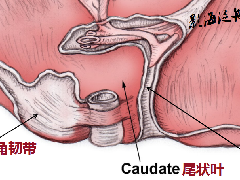

| 类 型 | 影像表现 | 小 结 |

| 脂肪浸润(图1〜图 3) | 肝脏密度弥漫性减低。在肝脏脂肪变的低密度背景下,门静脉表现为高密度结构(平扫时正常门静脉呈低密度)。 | 由于三酰甘油过度沉积所致,见于肝硬化或其他肝脏疾病。正常肝脏平均CT值不低于脾脏,肝脏脂肪 浸润时CT密度较低。肝硬化引起脂肪浸润,伴有肝右叶萎缩,尾状叶体积增大。 |

图1肝硬化患者的肝内脂肪浸润